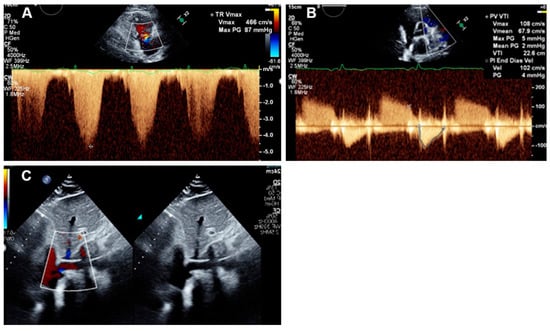

2.2. Echocardiographic Measurements